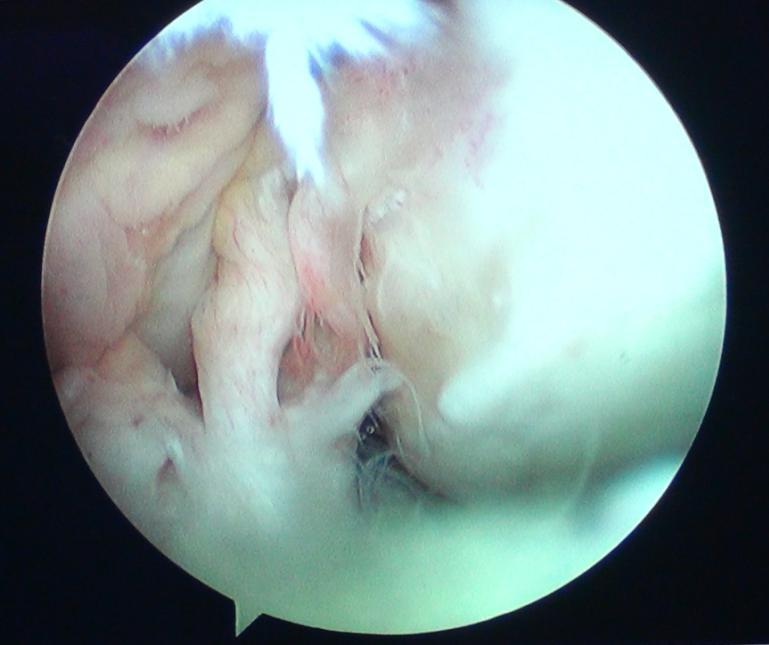

前交叉韧带断裂图片

前十字韧带断裂图片